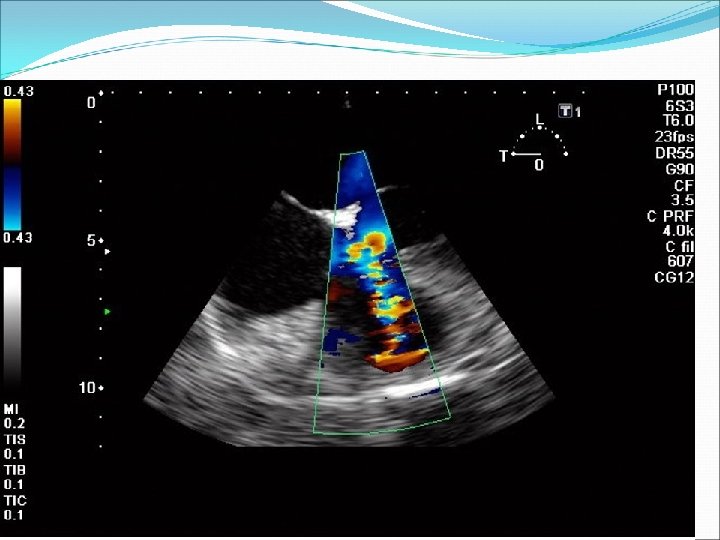

Defekt síňového septa: diagnostika echokardiografie, často jícnová: dilatovaná pravá komora zkratový proud barevným dopplerovským vyšetřením při přítomnosti trikuspidální regurgitace neinvazivně z rychlosti regurgitace odhadovat výši systolického tlaku v plicnici kalkulovat systémový průtok(Qs) ve výtokovém traktu levé komory a plicní průtok(Qp) v kmeni plicnice a počítat jejich poměr EKG: obraz bloku pravého raménka Tawarova u 95 % pacientů je projevem opožděné aktivace dilatované pravé komory Skiagram hrudníku : dilatace pravé komory, pravé síně, dilatace plicnice, zvýšenou plicní kresbu. Katetrizační vyšetření : před uzávěrem defektu u starších pacientů k posouzení plicní vaskulární rezistence a k provedení selektivní koronarografie.